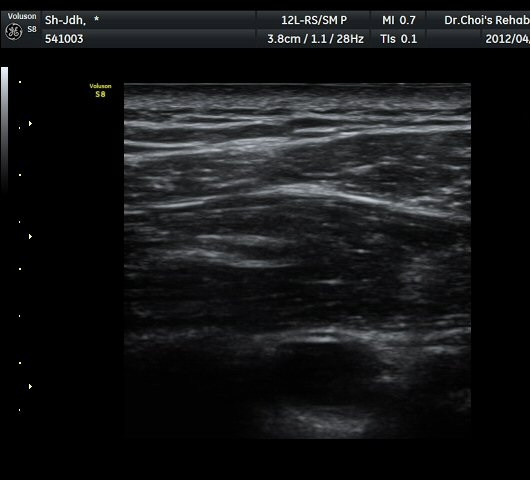

À̵ιڱ٠Ⱦ´Ü¸é°Ë»ç¿¡¼­ À̵ιڱٰÇÀÇ ºñÈĸ¦ º¸ÀÓ(»çÁø 1, 2).

À̵ιڱٰú ÀÌ¿ôÇÑ °ß°©ÇÏ±Ù°Ç »óºÎ¿¡¼­ ±¹¼ÒÀûÀÎ ¿¬°á¼º ¼Ò½ÇÀÌ °üÂûµÊ(»çÁø 3).